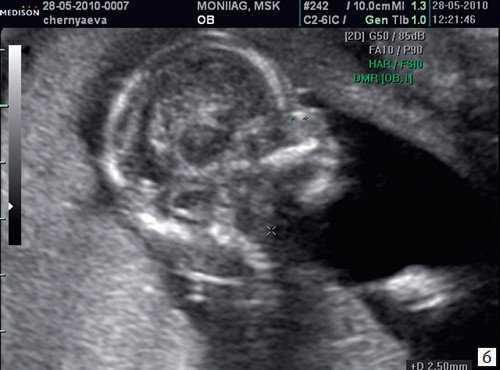

Цель 3D-ультразвукового исследования состоит в создании объемного изображения в отличие от двухмерного метода, создающего плоскостные сечения [6, 11]. Объемная картина получается при сканировании смежных сечений — это объем пространства пирамидальной формы (рис. 3, 4).

Рис. 3. Плод, 31 неделя, 3D-ультразвуковое исследование / Fig. 3. Fetus, 31 weeks, 3D

Рис. 4. Плод, 32 недели, 3D-ультразвуковое исследование / Fig. 4. Fetus, 32 weeks, 3D

Время сканирования в среднем составляет от 3 до 10 с в зависимости от важности объемной информации и требуемого качества изображения.